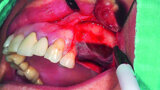

Fig. 15: Combination of full- and partial-thickness flap elevation.

Fig. 16: Mandibular ridge splitting with vertical cuts.